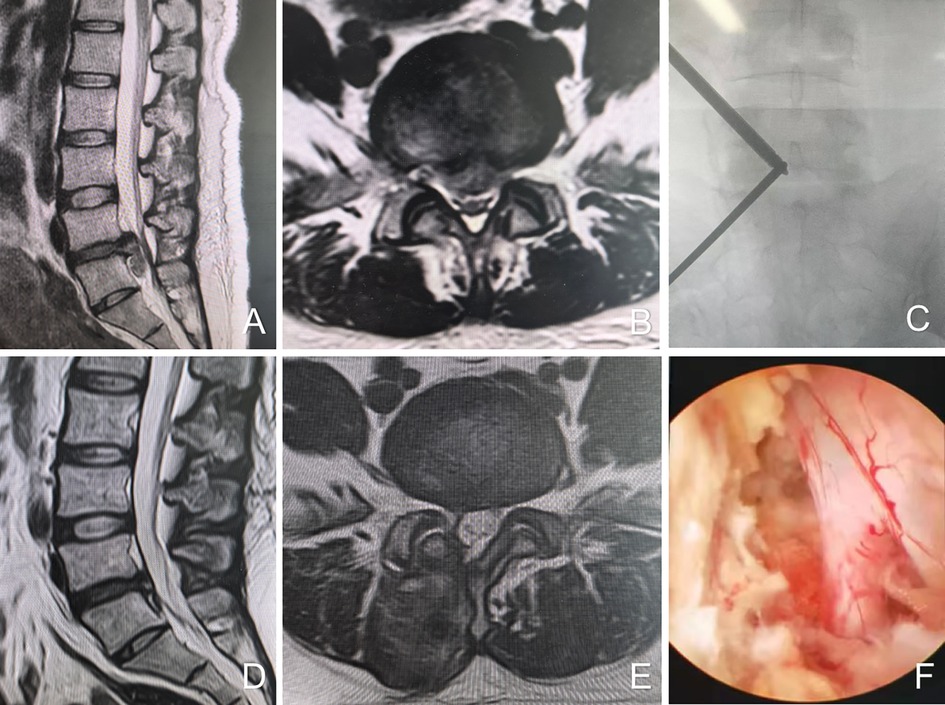

A T-shaped dilator is employed for blunt dissection of the soft tissue. The cranial portal (observation channel) is utilized for the insertion of the endoscope (Stryker, Kalamazoo, MI, USA) to provide visualization, while the caudal portal (working channel) serves for the introduction of surgical instruments and radiofrequency (RF) ablation equipment (BONSS, Jiangsu, China). RF ablation and pituitary forceps are used to clear soft tissue within the visual field, thereby exposing the superior and inferior laminae, articular processes, and the base of the spinous process. Partial laminotomy is performed using a high-speed grinding drill (Xishan, Tianjin, China) and Kerrison punches to expose the insertion site of the ligamentum flavum. The ligamentum flavum is resected using Kerrison punches to reveal the underlying dura mater and nerve roots. With gentle medial retraction of the traversing nerve root, discectomy is performed using pituitary forceps. A neural probing hook is employed to confirm the absence of residual disc fragments. Following meticulous hemostasis, a drainage tube is placed, and the surgical incisions are closed with sutures (Figure 1).

Figure 1. Female, 39 years old, L5/S1 lumbar disc herniation. (A) Preoperative sagittal MR image showed L5/S1 lumbar disc herniation; (B) preoperative axial MR image showed herniated lumbar disc compressed nerve root and dural sac; (C) intraoperative fluoroscopic confirmation of metal rods; (D) postoperative sagittal MR image shows complete decompression of the spinal canal, but with intraspinal adhesions; (E) postoperative axial MR image showed the complete removal of herniated disc and bony fragment; (F) intraoperative image after complete neural decompression.